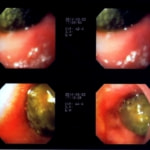

主訴:8ヶ月前から便が細くなり、血が混じることがある。その他、元気・食欲等、一般状態は良好。

経過:超音波検査にて直腸壁の肥厚(5㎜)が認められた。また、直腸検査で直腸全周に結節状病変を触知し、出血も確認された。消炎剤、抗生剤、整腸剤による治療への反応が長期的に悪いため、生検も含めた内視鏡検査を実施した。

内視鏡検査:肛門付近の直腸全周に、炎症および出血を伴う結節状病変を多数認めた。

病理検査:直腸の病変は、良性の非腫瘍性病変の一つである“炎症性ポリープ”と診断された。

診断後経過:炎症性ポリープは多発する傾向や腫瘍に転化する可能性があるため、消炎剤、抗生剤、整腸剤による内科療法を継続しながら、現在プルスルー法による外科的摘出術を検討中。